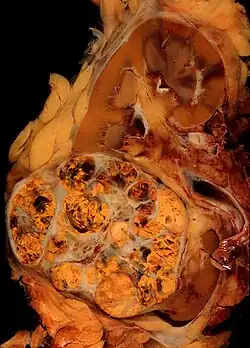

A renal cell carcinoma (lower left) in a kidney

Cancer immunotherapy refers to a diverse set of therapeutic strategies designed to induce the patient's own immune system to fight the tumor. Contemporary methods for generating an immune response against tumors include intravesical BCG immunotherapy for superficial bladder cancer, and use of interferons and other cytokines to induce an immune response in renal cell carcinoma and melanoma patients. Cancer vaccines to generate specific immune responses are the subject of intensive research for a number of tumors, notably malignant melanoma and renal cell carcinoma. Sipuleucel-T is a vaccine-like strategy for prostate cancer in which dendritic cells from the patient are loaded with prostatic acid phosphatase peptides to induce a specific immune response against prostate-derived cells. It gained FDA approval in 2010.